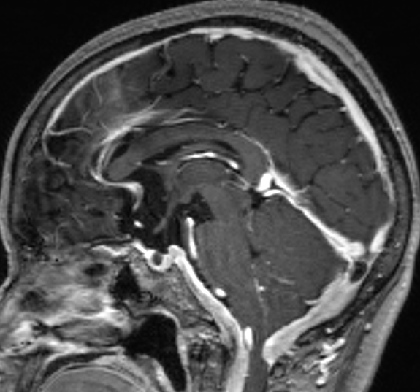

2013-5-16 MRI